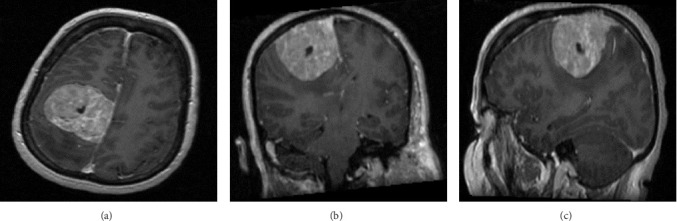

Background and importance: Meningiomas are one of the most frequent primary central nervous system (CNS) tumors. According to the World Health Organization (WHO) classification of brain tumors, meningiomas are categorized into Grade 1 (benign meningioma; 80%), Grade 2 (atypical meningioma; 4%-15%), and Grade 3 (anaplastic meningiomas; 1%-3%). Grade 2 meningioma has a higher recurrence rate, ranging from 29%-52%. However, the transformation from atypical meningioma into benign meningioma is poorly understood. The present article describes a patient with Grade 2 meningioma that transformed into a benign subtype. Case presentation: A 51-year-old female with a history of seizures, presented with left-sided progressive weakness. Radiological imaging revealed a large extra-axial parasagittal lesion measuring 5 cm × 5 cm × 4.8 cm, suggestive of meningioma. The patient underwent subtotal resection of the lesion. Histologically, the tumor was in favor of Grade 2 meningioma. Radiological follow-up 8 years postoperatively revealed a recurrent meningioma. The patient underwent right-sided craniotomy and resection of the parasagittal meningioma. The histopathological features were suggestive of a Grade 1 meningioma. Conclusion: The transformation from atypical to benign meningiomas is rarely reported and the mechanism remains unclear. The present case provides insights into the natural history of this entity, describes possible etiologies, and lists the surgical management with an emphasis on preoperative radiological imaging and histopathological investigations.